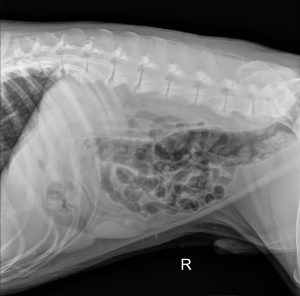

Pe scurt, despre invaginația intestinală la câini și pisici: Ce este: Invaginația intestinală este o [...]